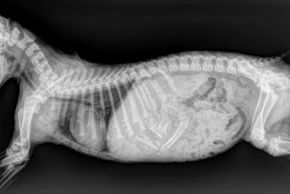

Mon chien doit faire une radiographie

Saviez-vous que la radiographie du chien est la technique d’imagerie médicale la plus pratiquée en médecine vétérinaire ? En effet, au cours de la vie de votre boule de poils, vous allez probablement devoir lui faire passer une radio. D’où l’intérêt de se familiariser avec cette méthode d’examen. Comment se déroule une radiographie ? Dans quel cas est-elle conseillée ? Et combien vous coûte-t-elle ? Mouss vous dit tout !